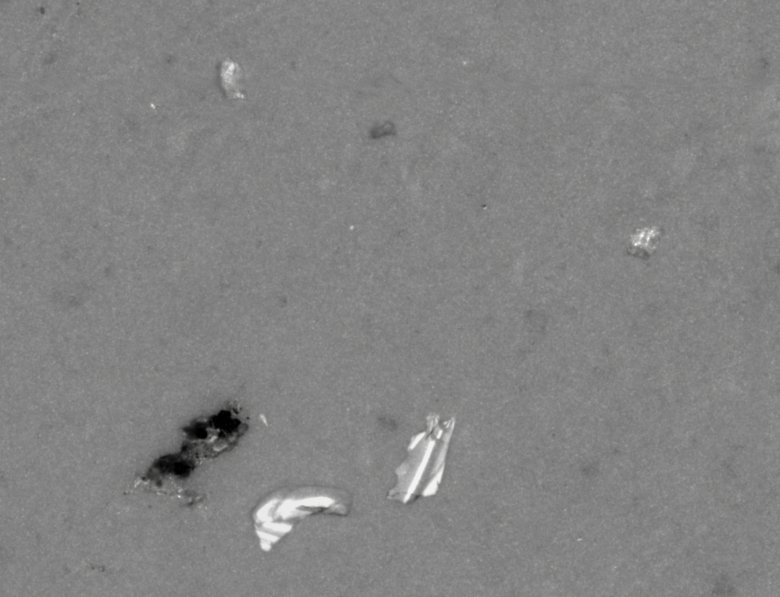

下面我將為大家呈現(xiàn)顯微計數(shù)法不溶性微粒儀下注射劑中微粒的聚集現(xiàn)象:

由圖可見,注射用乳劑隨著時間的流逝其中不溶性微粒已經(jīng)發(fā)生了聚集現(xiàn)象,2-10μm的粒子已經(jīng)長大到10μm以上,甚至25μm以上,足以堵塞人體的靜脈血管。

顯微鏡下的顆粒形貌

如上圖,是某在研注射液在顯微計數(shù)法不溶性微粒儀下的真實照片,可見其中有金屬顆粒和橡膠顆粒,顆粒粒徑<50μm,為肉眼不可見。所以我們認為的澄清注射液中卻大有乾坤。這些不溶性微粒經(jīng)過注射器就會進入我們的血管,然后通過血液流動而流經(jīng)全身,且無法被人體溶解和腎臟排出,從而造成血管壁的聚集和堵塞,造成血栓,是藥三分段,用錯藥錯用藥很容易治病不成而造成二次傷害。